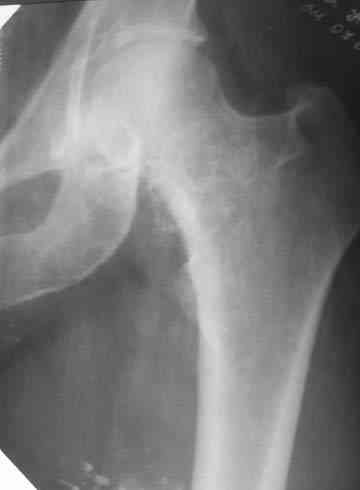

нормы. Рентгенологическое исследование. В прямой и боковой

проекции левого тазобедренного сустава отмечается уплотнение крыши

вертлужной впадины. В мягких тканях определяются округлой формы участки

неравномерного обызвествления.

Заключение. ДОА тазобедренного сустава. Хондроматоз слева в мягких тканях.